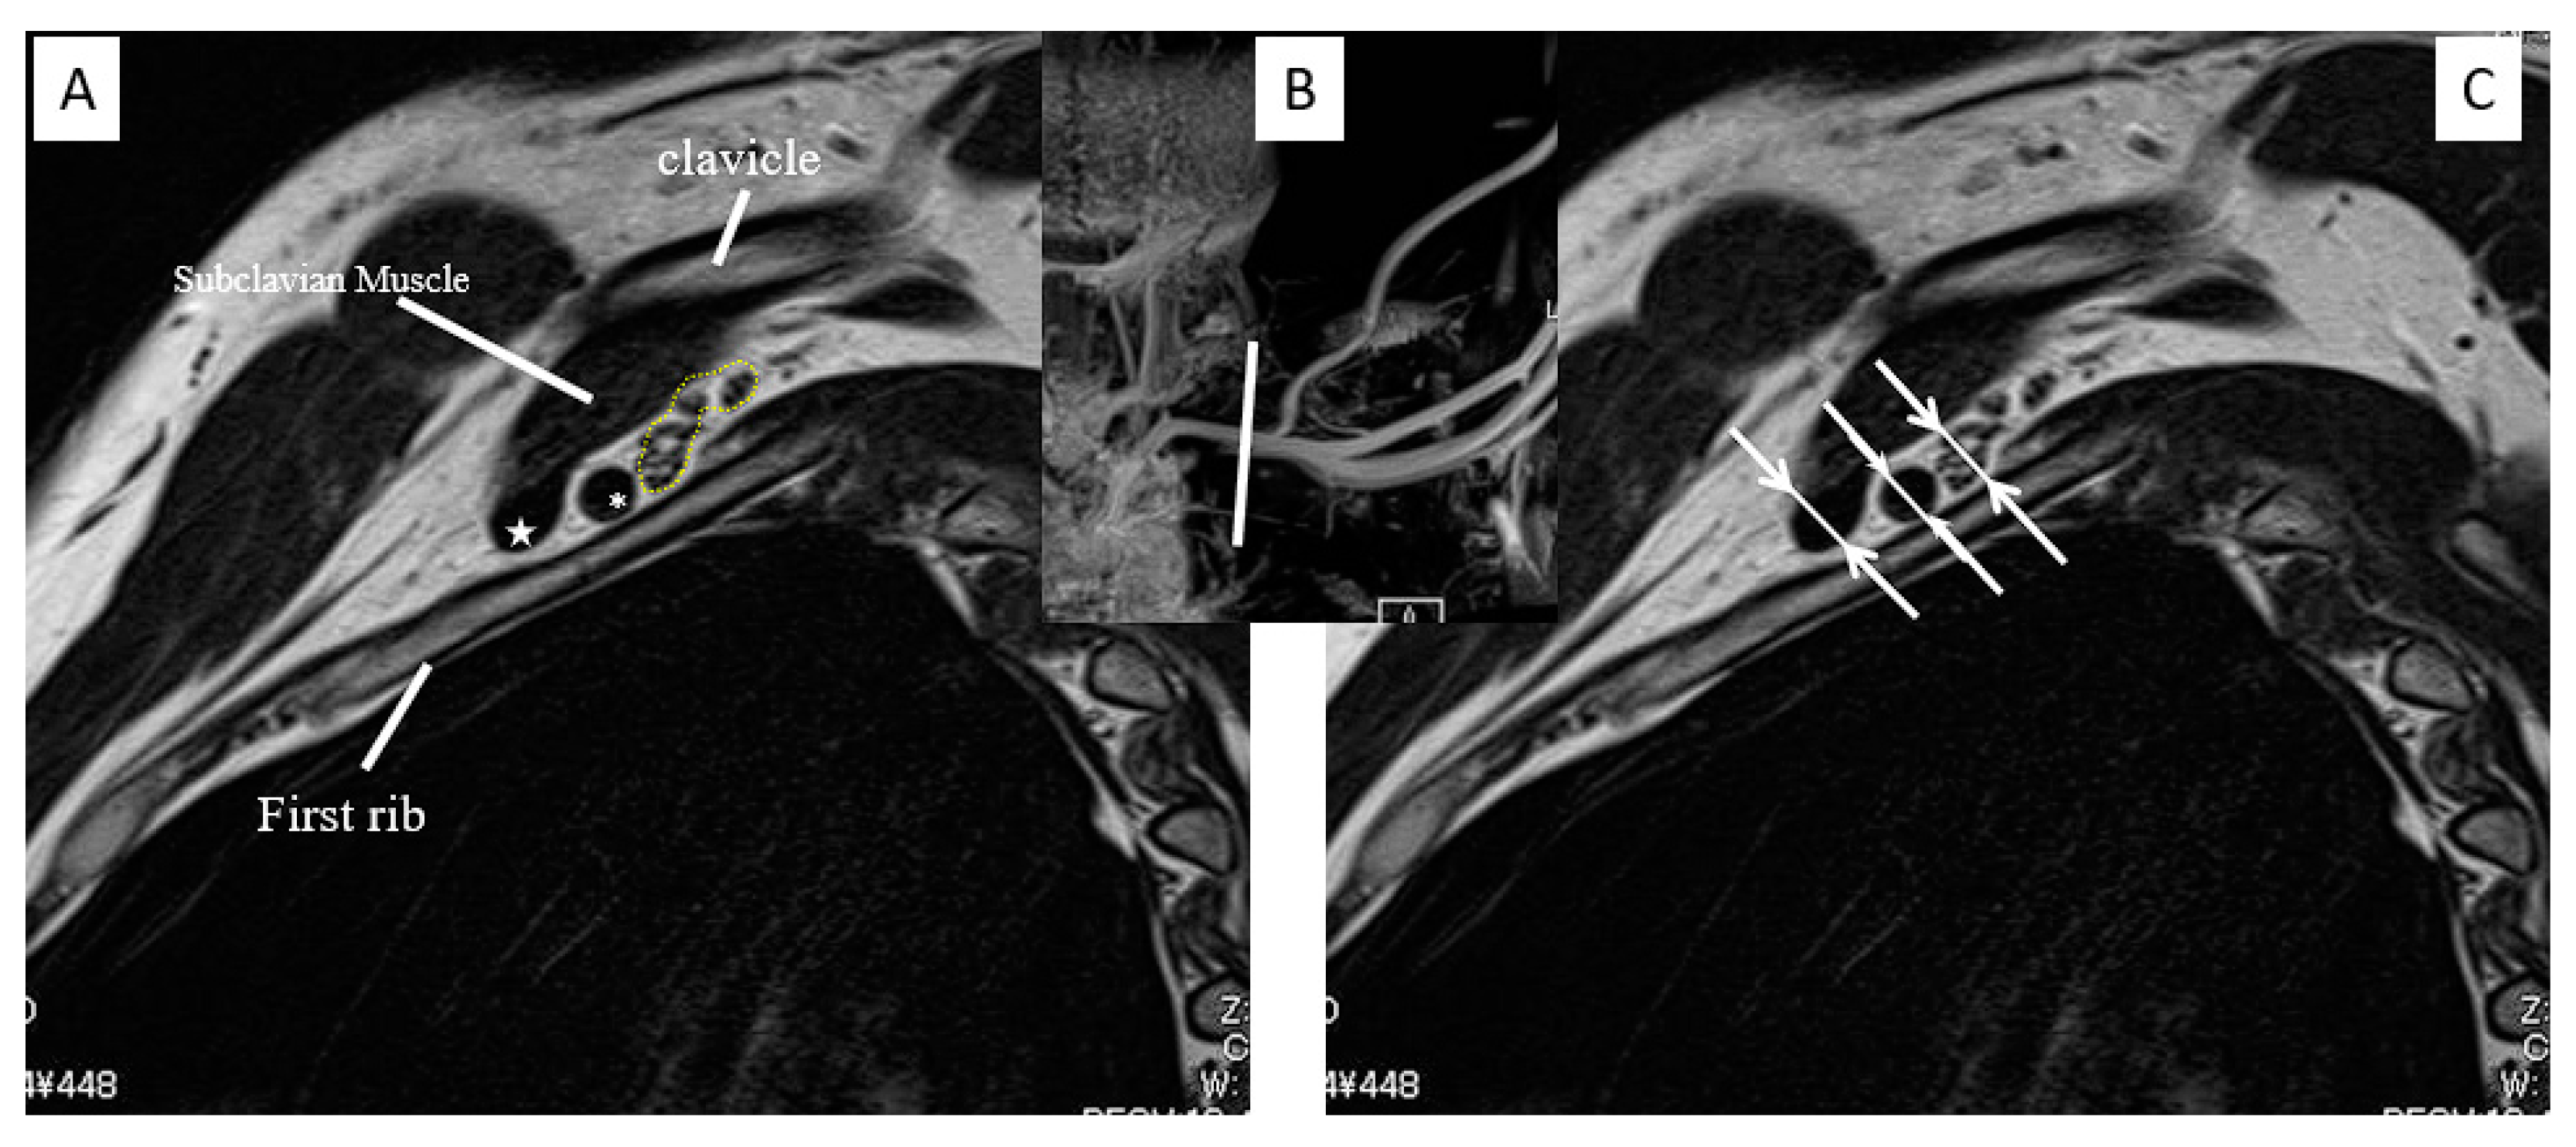

Representative Case